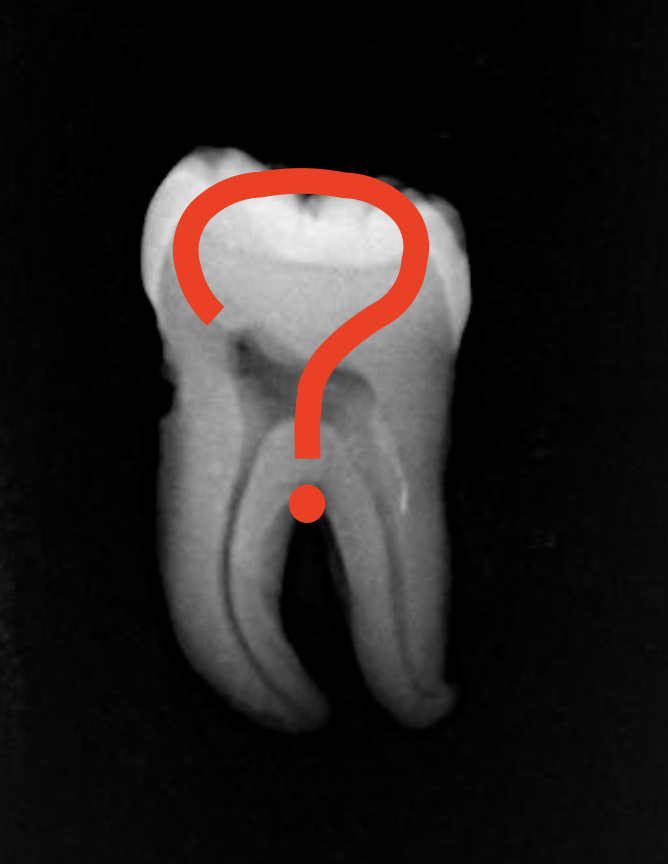

その後にX線検査やCT検査など必要に応じて画像検査を行います。